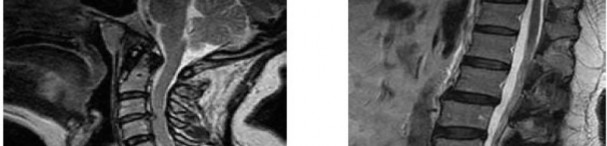

Question 7

A 65-year-old man presents with progressive clumsiness in his hands, difficulty buttoning his shirt, and a broad-based gait. A T2-weighted MRI shows spinal cord compression with intrinsic cord signal change at C4-C5.

Which of the following MRI findings is associated with the poorest prognosis for neurological recovery after surgical decompression in cervical spondylotic myelopathy?

Explanation

In cervical spondylotic myelopathy, the presence of T1 hypointensity corresponding to a T2 hyperintense lesion indicates myelomalacia or cystic necrosis of the spinal cord. This finding is a strong predictor of poor functional recovery following surgical decompression.